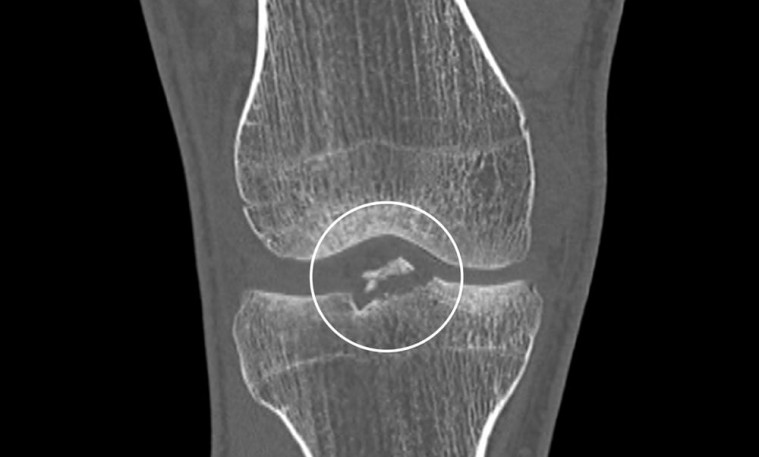

Богдан Богдановичийн аймшигтай гэмтэл